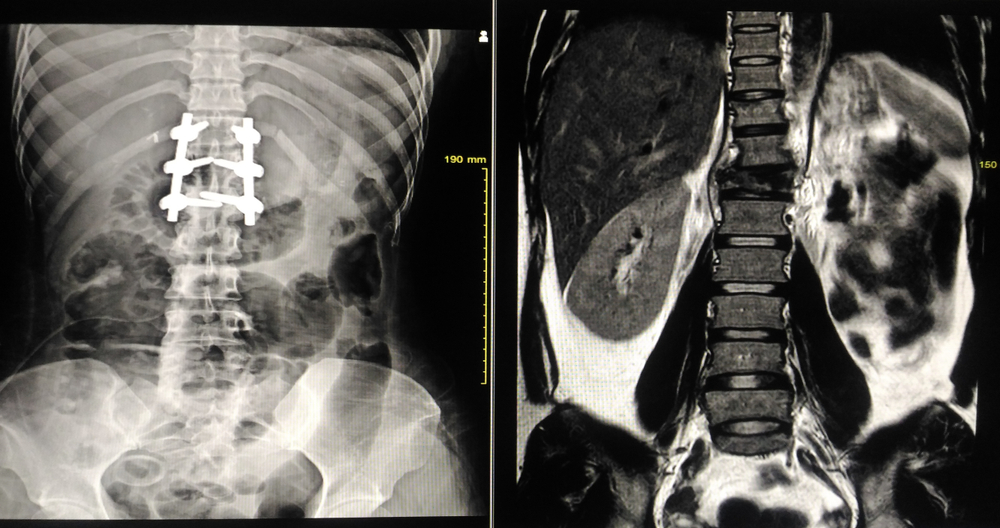

The MRI scan results showed signs of spondylodiscitis (an infection of the vertebra disc) along with an abscess and swelling of the spinal cord. A spinal biopsy was arranged, with the decision to hold off any antibiotics treatment until the biopsy was complete.

A further MRI scan showed progressing infection and a collapsed vertebra along with severe spinal compression. Following an urgent spinal opinion, BC underwent urgent spinal decompression surgery.